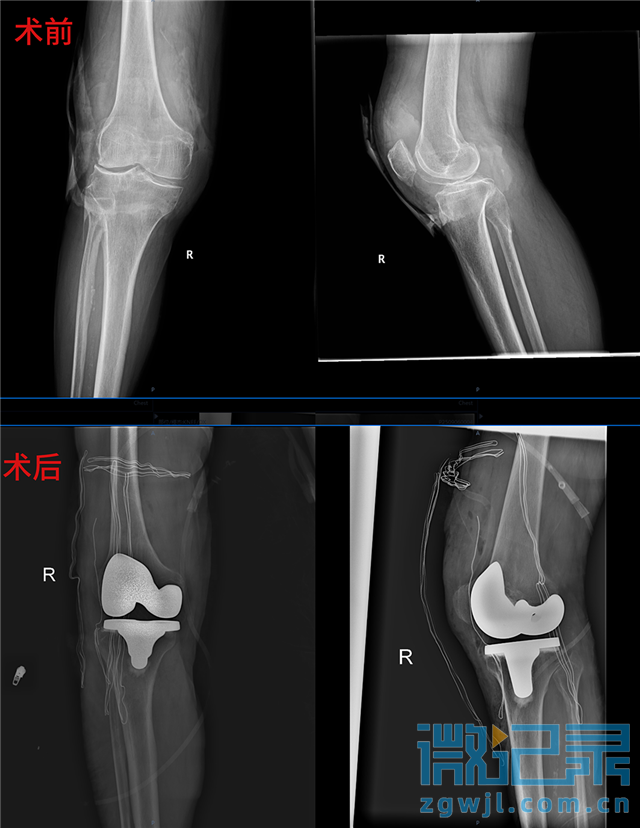

术前术后对比

在关节一科精心的准备下,顺利为颜爷爷完成了右侧全膝关节置换术。术后,还配合中医活血化瘀治疗和个性化的功能锻炼指导,多管齐下促进康复。出院时,颜爷爷的右膝疼痛已明显缓解,关节活动度恢复到90°,重新迈出了稳健的步伐。